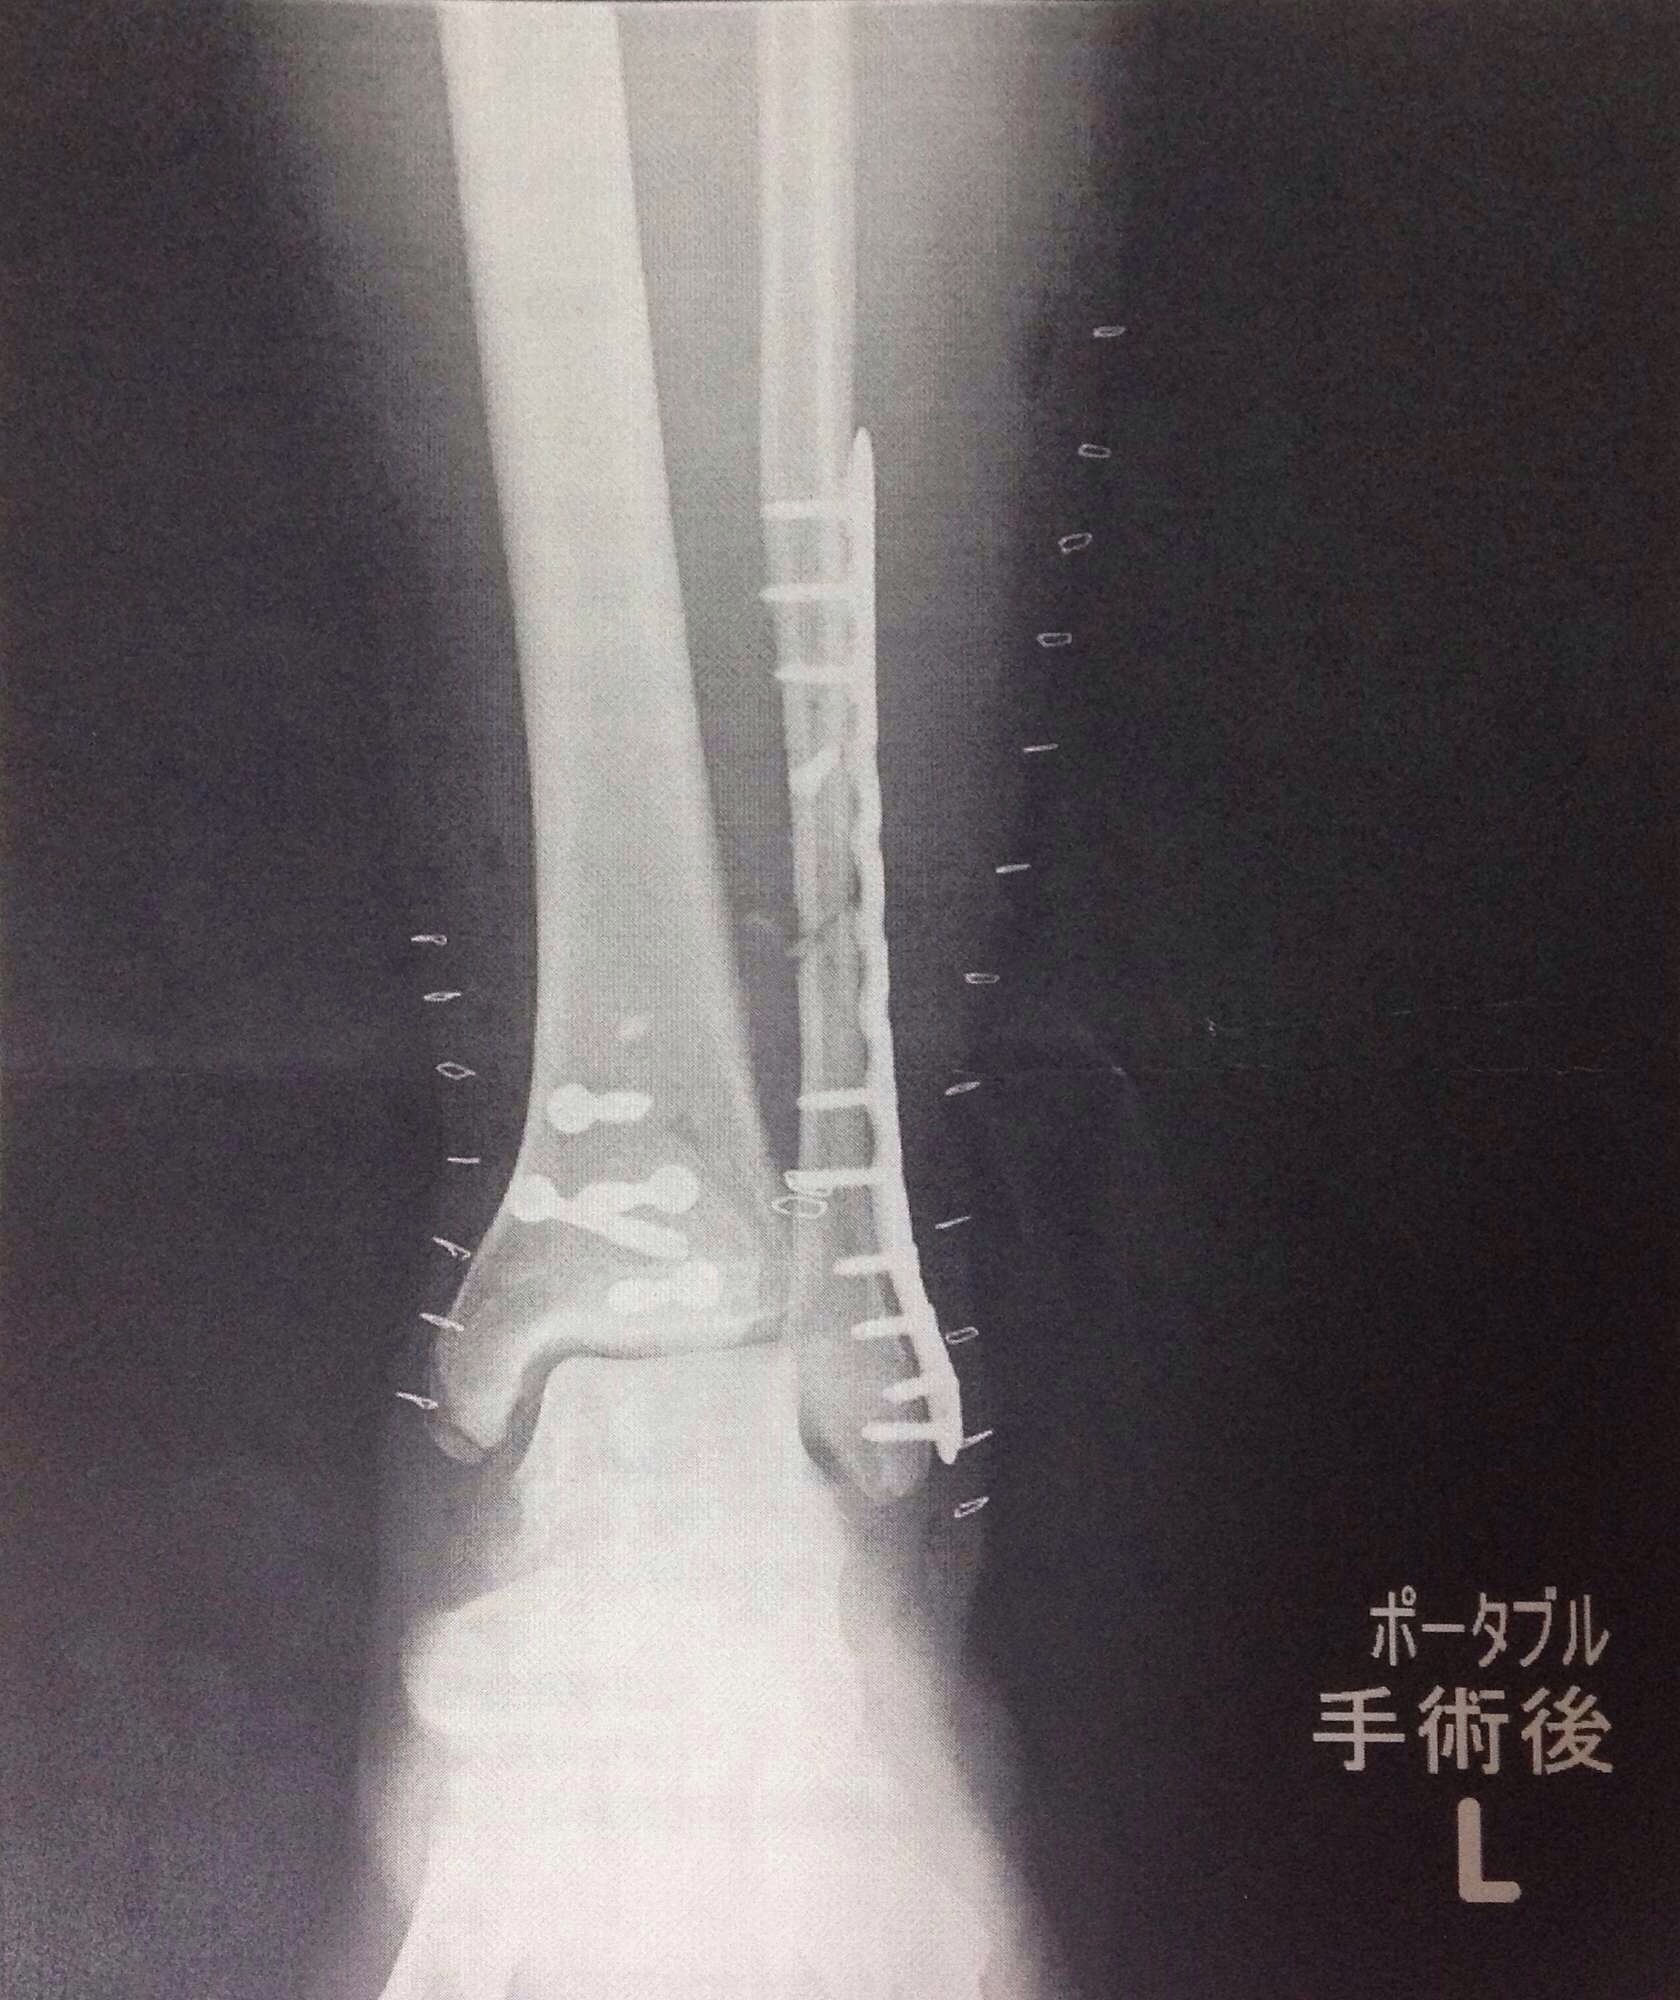

続いて左足首

左足首を正面から見たところです。

右側の縦に長いのが腓骨を固定しているプレートで、ネジでしっかりと固定されています。脚の輪郭に沿っているのは傷口をとめているステープラー(ホッチキスみたいなもの)

真ん中辺りにぽつぽつあるネジは、いろいろ割れているカカトの骨を固定しているネジです。左右から開いて手術しています。